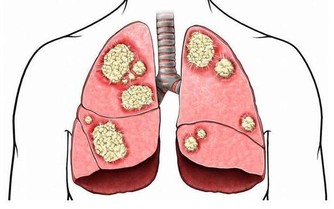

身邊受痛風困擾的朋友越來越多,這種常發生在中老年人身上的疾病,如今在20幾歲的年輕人身上竟也經常發生了,好可怕,防痛風,你我都要知道一點...... 痛風:是一種因長期嘌呤代謝紊亂,血尿酸增高而引起的疾病,是我國中老年人較常見的代謝性疾病。臨床表現急性關節炎反復發作,痛風結石形成,關節畸形,痛風性腎病,甚至腎功能衰竭。

痛風,是由於體內嘌呤代謝紊亂所引起的一類疾病。因其起病急驟,來勢如風,疼痛劇烈,多伴紅腫,走時較快,不留影蹤,故名痛風。該病的臨床特點是高尿酸血症,及由此引起的痛風性急性關節炎反復發作、痛風石沉積、痛風石性慢性關節炎和關節畸形。常累及腎臟引起慢性間質性腎炎和尿酸性腎結石,並引起腎功能損害,累及血管可以引起高血壓,累及心臟可以引起冠心病,並且常常伴發高脂血症、糖尿病等疾病。

因此,儘管痛風多表現在關節引起關節炎,但實際上它是一種全身病變,可引起多髒器損害,甚至危及生命,因此,必須引起高度重視。